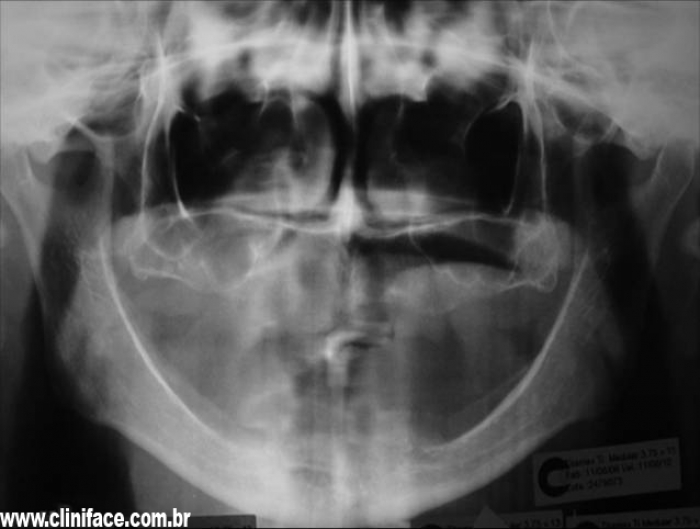

Raio X inicial